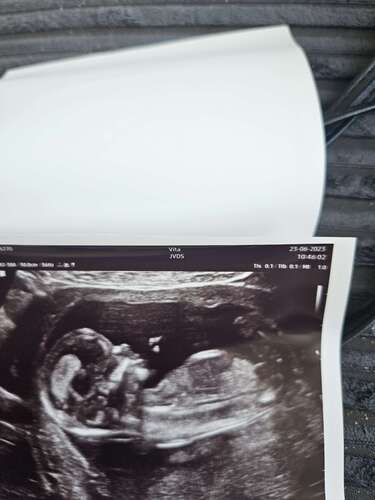

Iemand enige idee? Heel erg bedankt alvast 🥰

Iemand een idee?🥰

Iemand een idee wat het zou zijn?🩷💙 op deze echo was ik 15+2🤗

Benieuwd wat jullie hier zeggen, echo is gemaakt met 12+2. Vrijdag controle echo bij de vk en als ze het niet kunnen zien maandag nog een pretecho

Toch even dubbelchecken… wat zien jullie hier?

Nog één poging, heb nog geen reactie gekregen wellicht door slechte foto. Hierbij ingezoomd. Heeft iemand een idee? Pas over 7 weken 20 wkn echo 🙏

Iemand enig idee?🩵🩷